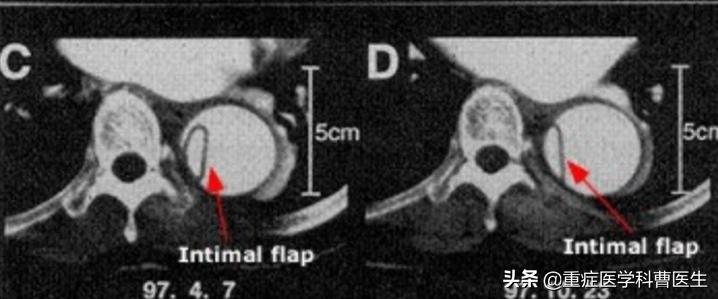

主动脉夹层的影像学诊断依据是内膜瓣从真腔中分隔出假腔,以及相关的并发症

- 内膜瓣

- 真腔和假腔